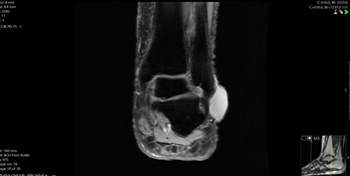

- Healthy vs Damaged cartilage – Arthroscopic view of healthy ankle cartilage on the right and damaged ankle joint on the left.